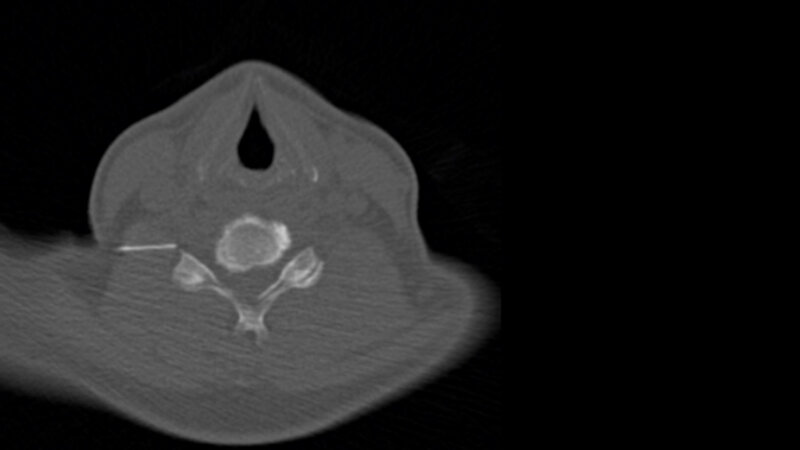

Frauen sind häufiger betroffen als Männer. Dabei unterscheidet man den akuten (bis 6 Wochen), subakuten (6–12 Wochen) und den chronischen (über 12 Wochen anhaltend) Rückenschmerz. Zur Behandlung dienen primär physikalische Therapiemaßnahmen und die Analgetikagabe. Bei anhaltender Symptomatik kommen zusätzlich weitere Therapieansätze, wie die CT-gestützte periradikuläre Therapie, zum Einsatz.

Die Grundlage zur Durchführung einer periradikulären Therapie bildet neben einer ausführlichen Anamnese und klinischen Untersuchungen auch die Erstellung einer geeigneten Bildgebung (MRT- und CT-Untersuchungen). Durch die Schnittbilder kann ein anatomisches Korrelat für die Schmerzen sowie die Stelle, an welcher die Nerven gereizt oder zusammengedrückt werden (zum Beispiel durch einen Prolaps oder Tumor), lokalisiert werden. Vor der PRT muss bekannt sein, welchen Nervenaustritt man behandeln möchte (Wirbelsäulenhöhe und Seite). Meistens erfolgt der Eingriff ambulant oder teilstationär, der/die Patient/-in kann nach der Behandlung wieder nach Hause gehen.